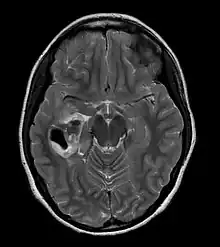

PXA as visualized on an MRI

PXA is diagnosed through a combination of diagnostic processes:

• A CT scan of the brain, and/or an MRI scan of the brain and spine, will be performed. A special dye may be injected into a vein before these scans to provide contrast and make tumors easier to see.